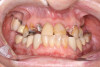

Fig 2. Initial presentation, intraoral view.

Figure 2

A 36-year-old male patient presented with a highly compromised maxillary dentition comprised of only teeth Nos. 4, 6, 7, 9, 10, 11, and 14 (Figure 1 and Figure 2). This poor condition was the result of only sporadic dental care with extractions and no teeth replacements. Soft tissues had normal contour, and bone profiles were generally sustained and favorable. The patient was excited about having the option to transform his compromised esthetics and function in one visit.